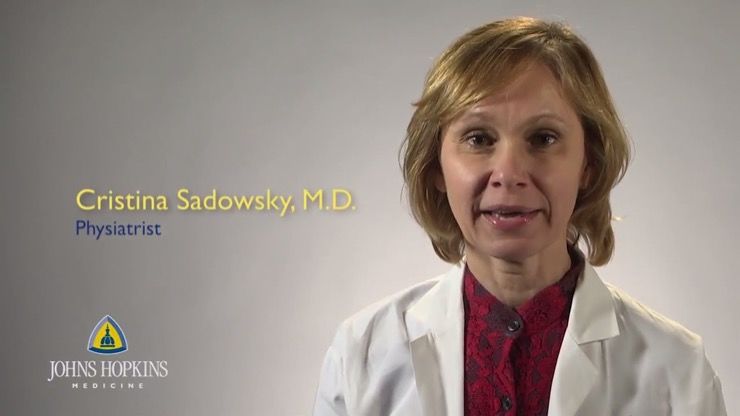

Really Excited

Medical experts are very excited about this breakthrough in their quest to help people who have suffered from spinal cord injuries. As Dr. Cristina Sadowsky from the Johns Hopkins University said, “I’m really excited about this.” However, she cautioned that while the procedure tapped into “residual connections that are not being used,” she added that, “not everybody who has a similar injury will respond the same.”